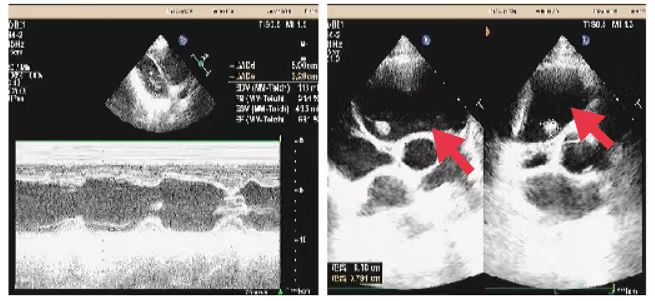

08、**女士,25岁

于2023年10月15日在邯郸仁泰西区体检,心脏彩超检查提示:前纵膈内囊性回声7.3cm*5.3cm,考虑纵膈囊肿,建议客户到三甲医院进一步检查。2023年10月25日跟踪回访,客户已在中心医院就诊,确诊纵膈囊肿拟手术治疗。